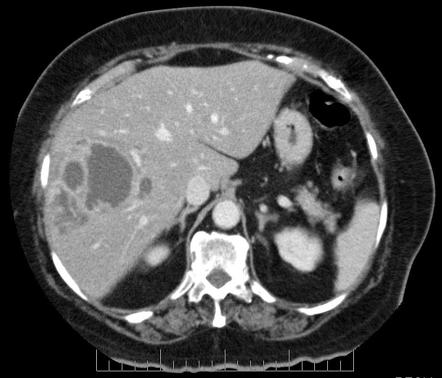

1/ Let's differentiate pyogenic from amebic liver abscess in a #Tweetorial today. We will examine DDx, risk factors, microbiology, clinical features, diagnostics, and treatment. This came from my most recent morning report. #IDTwitter #LiverTwitter #MedEd pic.twitter.com/IOZk3j1wht